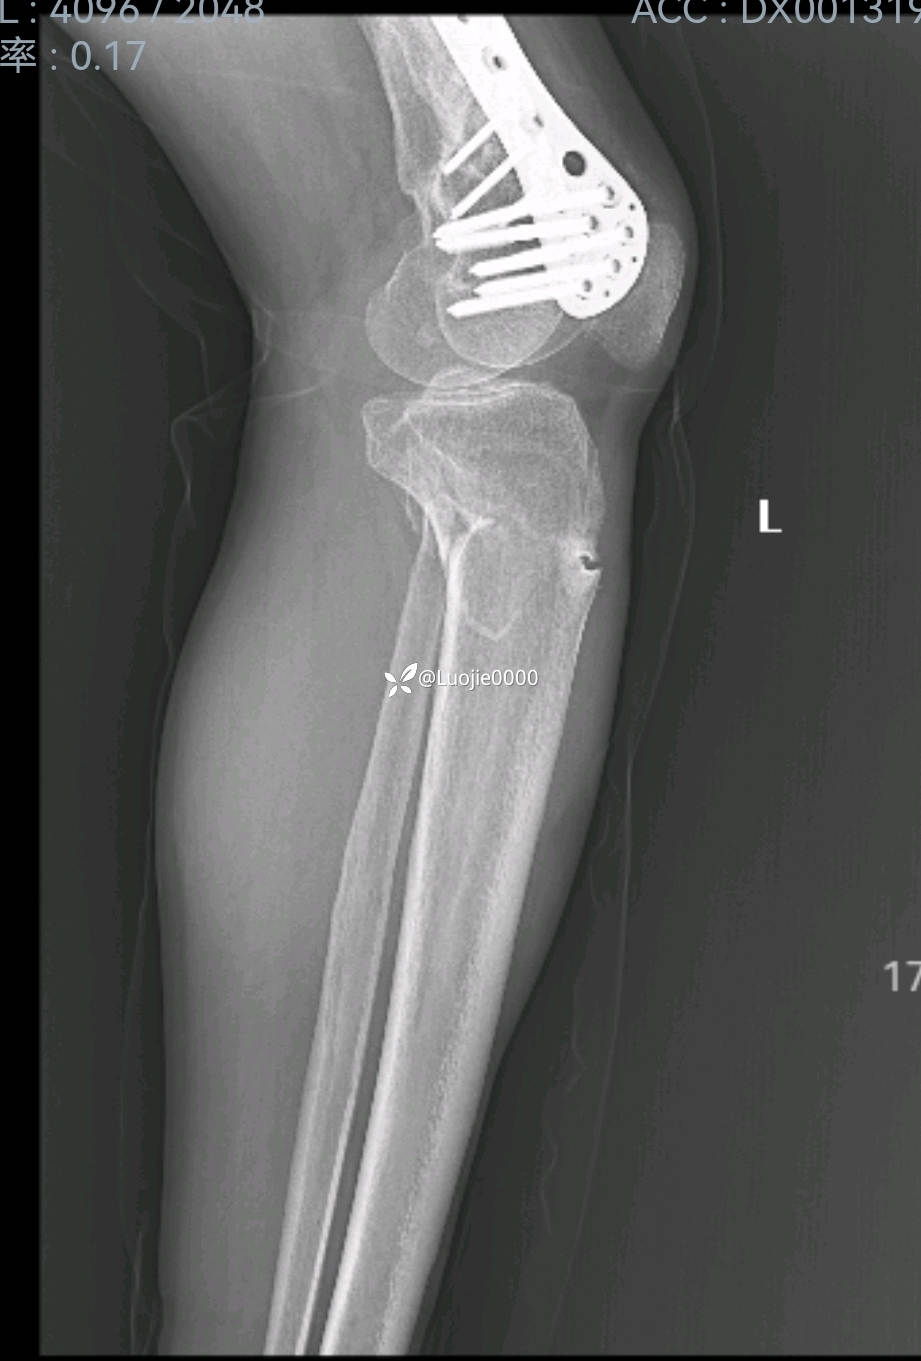

辅助检查:DR及CT提示:左胫骨近端及腓骨头骨折。

影像资料如下: